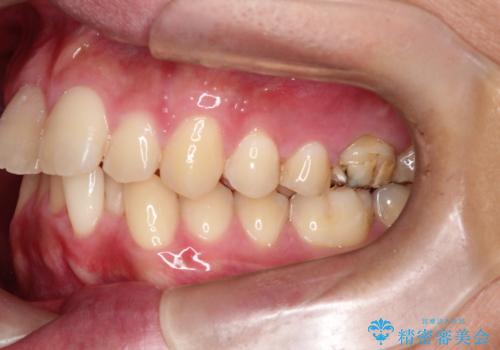

【インビザライン 非抜歯】歯の捻じれと歯のでこぼこを治したい!

- 「上の前歯の捻じれと下の前歯のでこぼこを治したい」を主訴に来院された患者様です。

矯正検査の結果、非抜歯で矯正可能だったためインビザラインで治療を行いました。

アーチの拡大とIPRで叢生を改善いました。

11ヵ月で矯正を終える事ができ患者様も大変ご満足されていました。